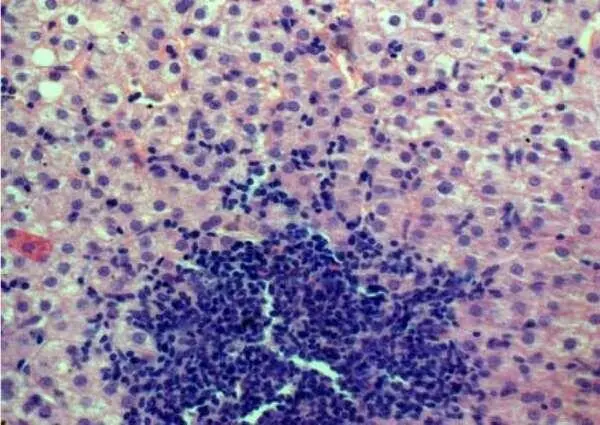

БП является наиболее точным методом в оценке активности воспаления и стадии фиброза при хронической НСV–инфекции. При анализе результатов БП больных НСV–инфекцией у 84,7% из них выявлен гепатит минимальной степени активности. Наиболее распространенным морфологическим признаком процесса была воспалительная инфильтрация портальных трактов (ВИПТ), представленная лимфоцитами и гистиоцитами (рис.22–23). ВИПТ отмечена в 100%, причем выраженная степень инфильтрации (3 и 4 балла по Кнодель) отмечена у 65 (51%) больных. Внутридольковые (лобулярные) некрозы (ЛН) выявлены у 56 (43,7%) больных, у 24 (18,8%) из них присутствовали ЛН выраженной степени (3 и 4 балла по Кнодель). Ступенчатые (перипортальные) некрозы (СН) отмечены у 55 (43%) больных, в том числе у 20 (15,6%) – резко выраженные.

Рисунок 22 – HCV умеренной степени активности: лимфоидная инфильтрация портального тракта с образованием фолликула; инфильтрат проникает в дольку; ступенчатые некрозы гепатоцитов; цепочки лимфоцитов в синусоидах. Окраска гематоксилином и эозином, Х100

Рисунок 23 – HCV умеренной степени активности: лимфоидная инфильтрация портального тракта с образованием фолликула; инфильтрат проникает в дольку; ступенчатые и внутридольковые некрозы гепатоцитов; деструкция и пролиферация желчных протоков; порто–портальная септа. Окраска гематоксилином и эозином, Х100.